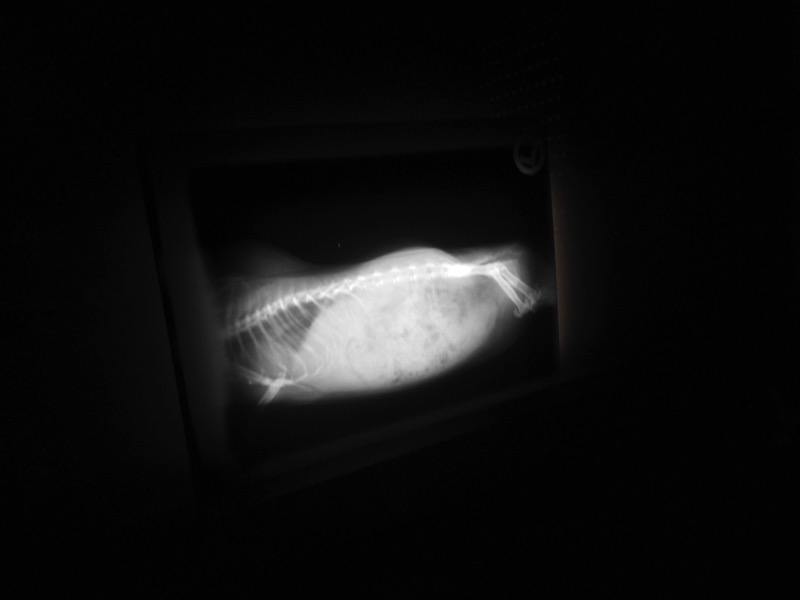

Eine Untersuchung mit Ultraschall ist ohne Narkose möglich und völlig schmerzfrei. Etwas stressig ist die Prozedur natürlich trotzdem für die Tiere - aber es ging alles sehr zügig und ist immer noch besser, als sich unerkannt krank im Gehege zu quälen. Viele Menschen wissen aus eigener Erfahrung um die schlimmen Schmerzen von Harnsteinen. Deshalb kann man auch privaten Tierhaltern nur empfehlen, ab und zu einen Tierarzt prüfen zu lassen.

Unsere Tiere waren alle ohne Befund. Ein Meerschweinchen musste zur genauen Abklärung noch geröntgt werden. So sind wir nun erst einmal wieder beruhigt.